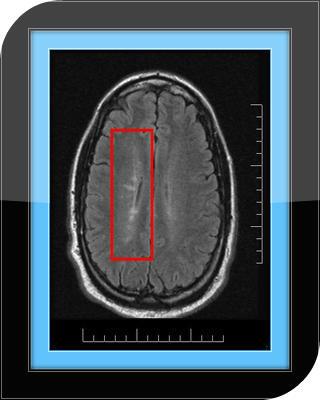

Brain Lesions: Everything You Need To Know

Studies show there is a correlation between brain lesion and language, speech, and category-specific disorders. However, lesions in Broca's and Wernicke's areas are not found to alter language comprehension.

Lesions to the fusiform gyrus often result in prosopagnosia, the inability to distinguish faces and other complex objects from each other.

Lesions to the visual cortex have different effects depending on the sub-area effected. Lesions to V1, for example, can cause blindness in different areas of the brain depending on the size of the lesion and location relative to the calcarine fissure. Lesions to V4 can cause color-blindness, and bilateral lesions to V5 can cause the loss of the ability to perceive motion.